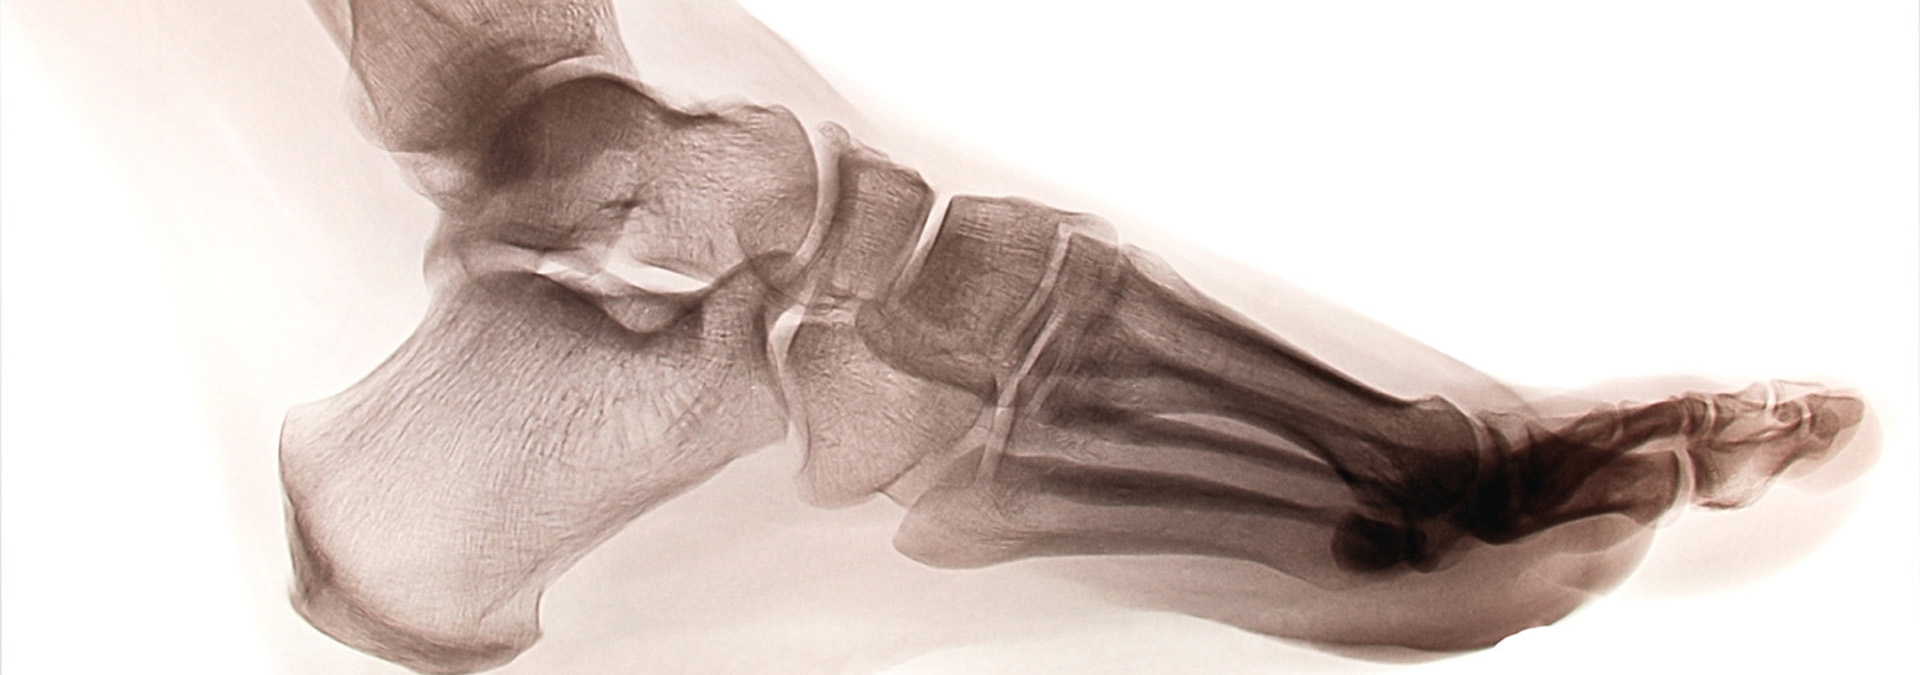

We focus on accurate diagnosis with on site diagnostic ultrasound.

Heel pain is the most common condition treated at the clinic.

Heel pain can be caused by:

- Plantar fasciitis

- Plantar fasciosis

- Bursitis

- Nerve inflammation

- Tendon damage/inflammation

- Fracture/stress fracture

We establish the cause of pain and establish a treatment plan to get you back to normal as soon as possible.